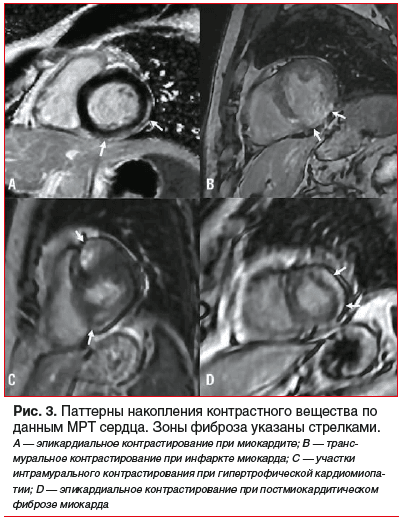

Применение нативных изображений, полученных с помощью магнитно-резонансной томографии (МРТ), для диагностики и характеристики ФМ ненадежно. Именно поэтому на практике применяется МРТ с контрастным усилением с помощью препаратов на основе гадолиния в режиме LGE — позднего усиления гадолинием [15]. Программы, предназначенные для выявления ФМ, выполняются на 10–15-й минуте после контрастирования (отсроченное контрастирование). Контрастные препараты на основе гадолиния свободно распространяются во внеклеточном объеме, не проникая через неповрежденную мембрану миоцитов. При повреждении кардиомиоцитов происходит нарушение целостности клеточных мембран, и парамагнетик проникает в клетки миокарда. В случае рубцов или фиброза препарат поступает в увеличенное межклеточное пространство и долго в нем задерживается. Следует отметить, что клетки здорового миокарда плотно прилежат друг к другу, а в случае замещения здоровой ткани соединительной тканью внеклеточный объем увеличивается [19]. Гадолиний укорачивает время релаксации Т1, что выглядит как гиперинтенсивный сигнал на МР-изображениях [18–20]. В зависимости от локализации фиксирования контрастного препарата можно косвенно судить о генезе фиброза (рис. 2, 3) [15].

В настоящее время LGE при проведении МРТ считают «золотым стандартом» неинвазивной диагностики ФМ. Основной недостаток этой методики — субъективность и высокая вариабельность результатов измерения. В отличие от фиброза вследствие ишемического повреждения миокарда, при неишемических кардиомиопатиях ФМ обычно имеет неоднородную структуру, а в ряде случаев отмечаются множественные очаги фиброза, что создает существенную проблему для его количественной оценки. Учитывая данные недостатки, растет интерес к созданию четких критериев для количественной оценки ФМ [21–23].